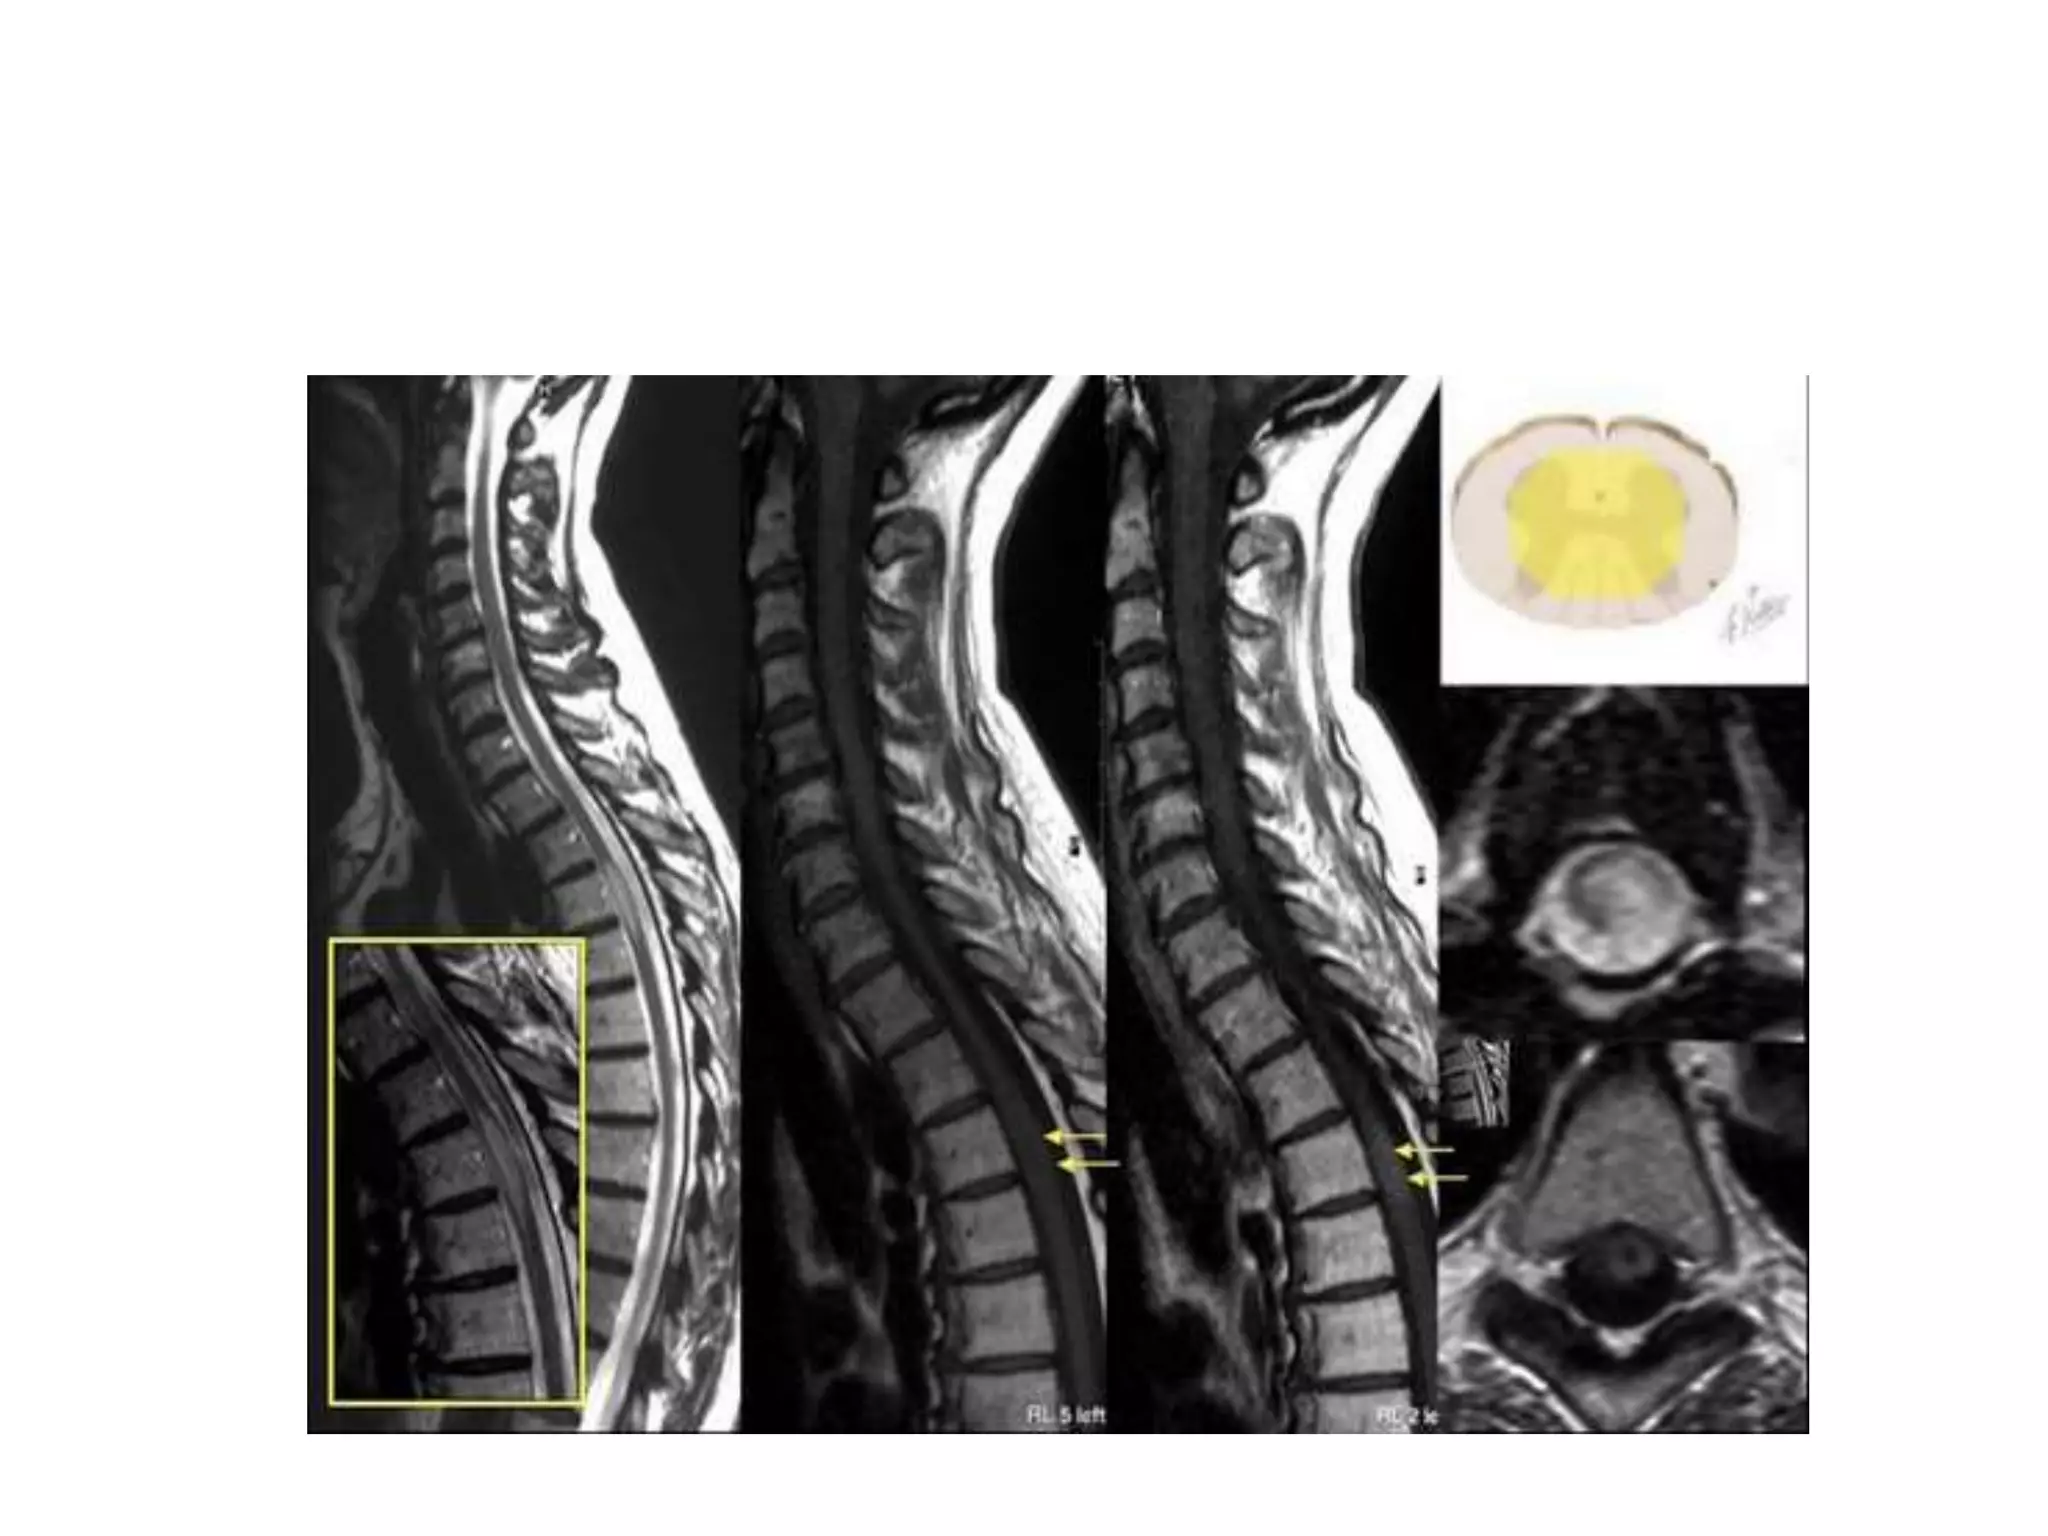

Mild spinal cord enlargement, with abnormal T2 Hyperintensity

within dorsal +/- lateral columns

Axial MR images display the symmetric involvement of the dorsal and

lateral columns as increased T2 signal in an “inverted V” or “inverted rabbit

ears” configuration in SACD.